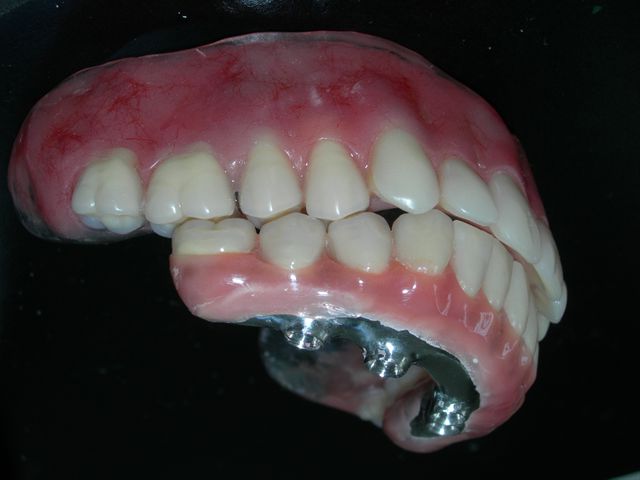

Protocolo acrilizada (VISTA SUPERIOR) |

Protocolo acrilizada (VISTA INFERIOR) |

Prova de articulação pós acrilização (fase laboratorial) |

Prova de articulação após acabamento (fase laboratorial) |